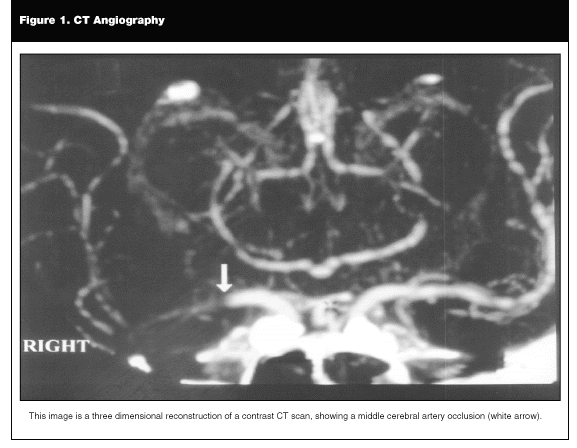

MRI with DWI (diffusion weighted imaging) may allow visualization of infarcts in the "hyperacute" stage. Unlike CT or standard MRI, in which stroke is not identified for up to 24 hours after symptom onset, DWI will reveal tissue ischemia within minutes. DWI abnormalities will disappear within 10 days after an infarct and, therefore, may be helpful in distinguishing between acute and chronic lesions. DWI is also sensitive for the presence of multiple lesions outside of the symptomatic territory. Other useful MRI techniques include MR angiography (MRA), which may visualize narrowed or occluded blood vessels, and perfusion weighted imaging (PWI), which may differentiate between tissue that is infarcted and salvageable tissue at risk.3,4 (See Figure 2.)